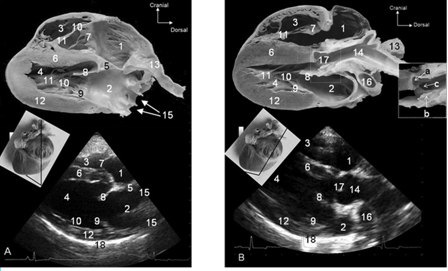

What view?

Right parasternal short axis views

What view of this?

What do we subjectively assess? (3)

–movement ventricles

–chamber dimensions

–valve morphology and motion

What do we quantitavely assess? (4)

–Left atrium diameter

–Aorta diameter

–Pulmonary artery diameter

–M-mode